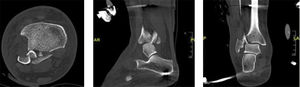

Radiografías y tomografía computarizada de luxofractura de Bosworth. A y B: radiografía de tobillo en proyección AP y lateral, respectivamente, donde se evidencia luxofractura trimaleolar. C y D: tomografía computarizada en cortes sagital y axial, respectivamente, donde se observa fragmento proximal de fíbula interpuesto en foco de fractura de maléolo posterior.

Durante las primeras 24 horas de la lesión, se diagnostica la luxofractura de Bosworth sospechando la lesión en las radiografías ortogonales del tobillo (figura 4) y se confirma con la realización de una TC la presencia de una luxación tibio-fibular distal con atrapamiento del fragmento proximal de la fíbula en el rasgo de fractura del maléolo posterior (figura 4).